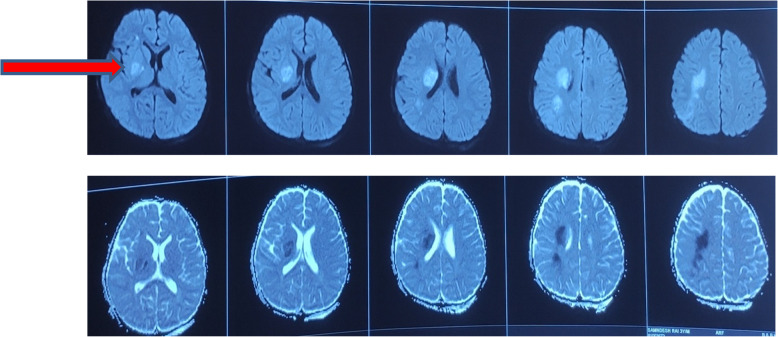

Case presentation: A 3 years old male with recent history of traumatic head injury following road traffic accident presented with weakness of left upper and lower limbs. On diagnostic evaluation there was right sided basal ganglia acute infarct. On further investigations basal ganglia infarct was secondary to moya moya disease. Patient was managed conservatively with single low dose anti platelets therapy, anti epileptic and was discharged with good functional outcome.